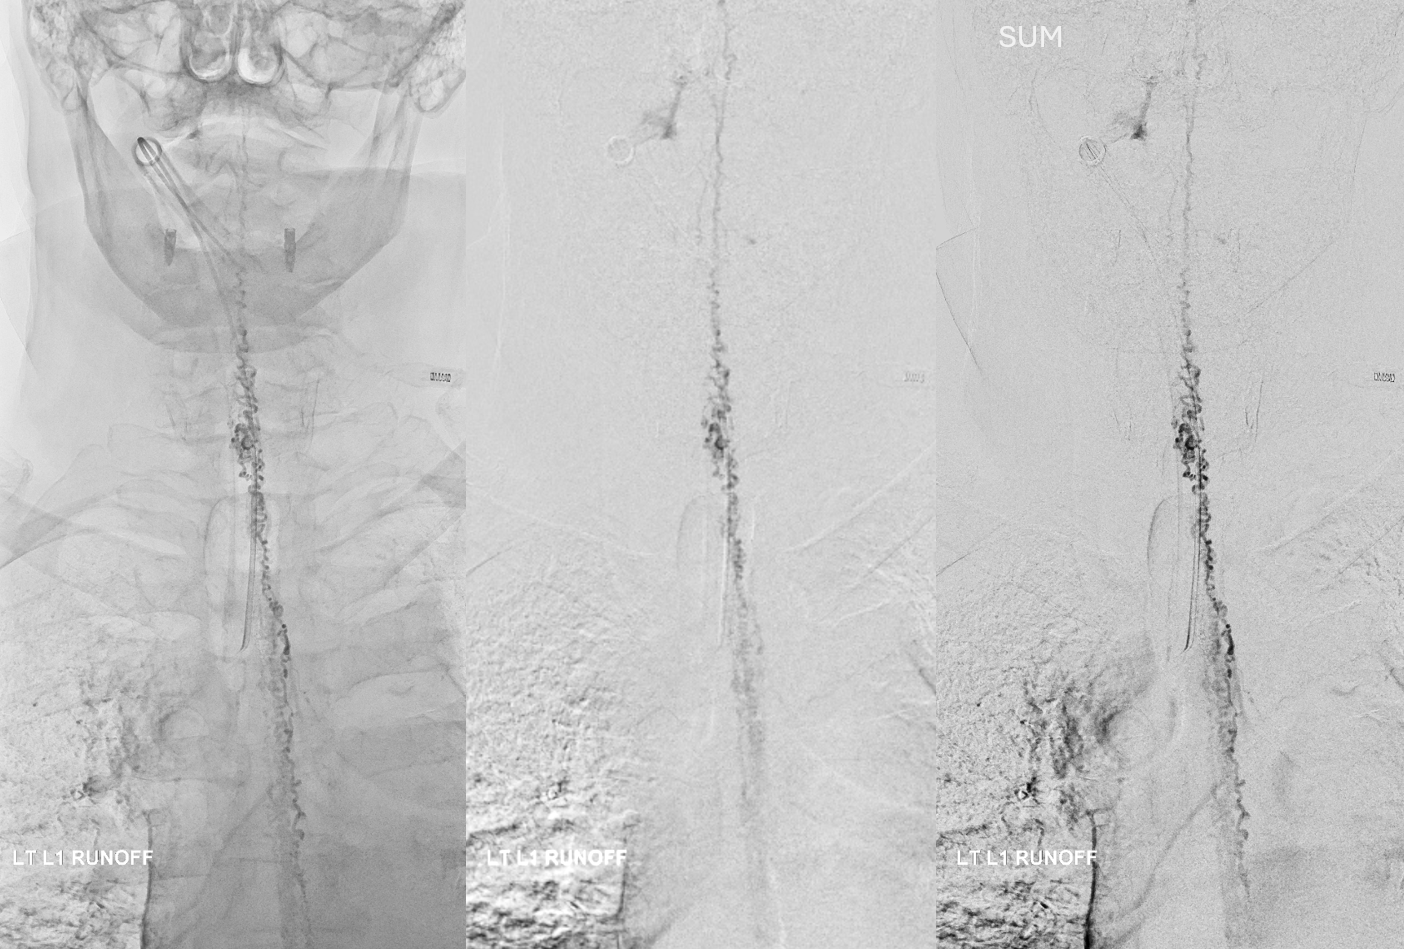

Post. It is important to control from other levels (left T12, left L2, and right L1) — not shown.

Key image here — injection of Adamkiewicz now shows return of the prodigal veins to the venous phase of the cord. Image on left also shows the now liberated basket.

pre and post Rx ASA views side by side

It is critical to understand cord venous drainage in post-dural fistula patients is never normal. The radicular veins are still missing. This may in part be responsible for the incomplete clinical recovery, although the main reason is probably cord damage before fistula occlusion.